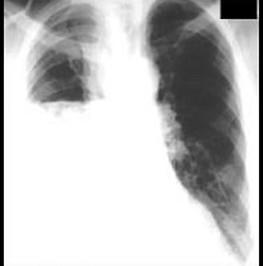

问题 女性,36岁,2个月前突然发热、咽痛、咳嗽、少量黄痰,经消炎治疗不见好转,一个月前,咳嗽加剧,并有呼吸困难,经两次胸穿抽出脓液300ml,症状不见好转,胸片如图,提示右侧胸腔有一液平,现应采取的治疗方法 ( )

选项 A、腋中线第7肋间闭式引流 B、腋前线第9肋间闭式引流 C、锁骨中线第2肋间闭式引流 D、胸穿排脓 E、消炎吸氧,输血补液

答案 A